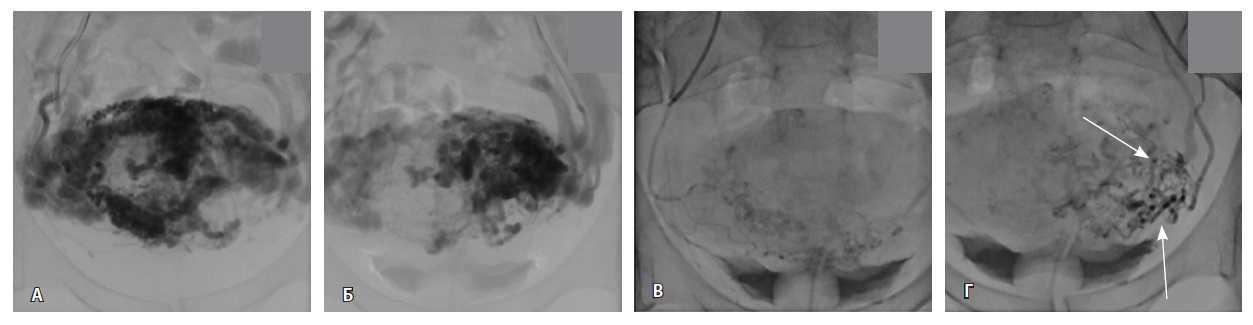

Выполнена эмболизация маточных и цервиковагинальных артерий с обеих сторон материалом PVA (1000 мкм) и эмболами из гемостатической губки. На контрольных ангиограммах патологическое сосудистое сплетение не контрастируется, артериовенозный сброс устранен (рис. 5). Катетеры и интродьюсер удалены, выполнен компрессионный гемостаз, наложена асептическая давящая повязка. Контрастный препарат йодиксанол (320 мг йода/мл) – 300 мл. Эффективная доза – 1,8 мЗв.

Рис. 5. Контрольные снимки после эмболизации маточных и цервиковагинальных артерий. Ангиограммы бассейнов правой и левой внутренних подвздошных артерий. Правая маточная и цервиковагинальная артерии, а также патологическое сосудистое сплетение в их бассейне не контрастируются, ранний артериовенозный сброс устранен. Незначительное контрастирование сегмента патологической сети по единичной мелкой ветви внутренней подвздошной артерии справа, по двум мелким ветвям внутренней подвздошной артерии слева (указано стрелками)